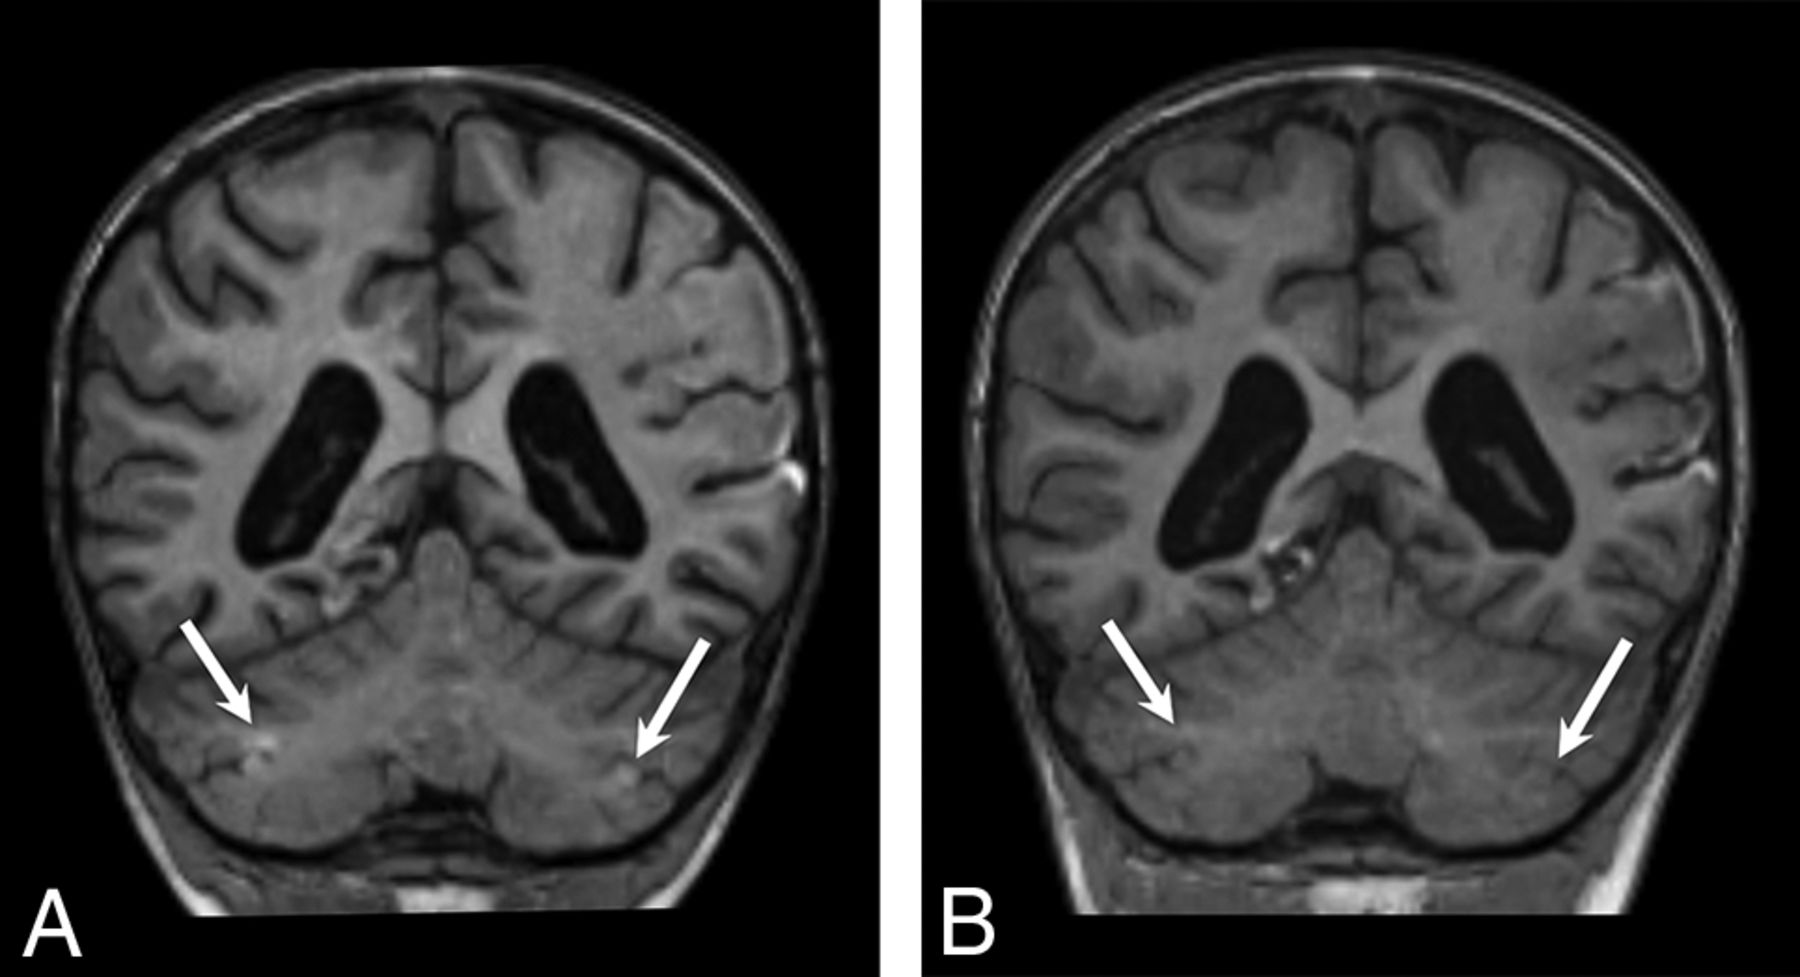

Imaging was available for 7/23 patients in the subacute phase of injury, defined as 7–30 days from the suspected clinical event. Three of 7 patients (patients 4, 18, and 22) demonstrated intrinsic T1 signal hyperintensity at the depths of the cerebellar fissures (Fig 5A). In 1 case, this was demonstrated to have resolved on a follow-up study performed 1 month later (patient 22) (Fig 5B). One patient who underwent contrast-enhanced MR imaging in the subacute phase demonstrated focal contrast enhancement in the areas of cerebellar injury (patient 18).

Coronal T1WI from patient 22 in the subacute (A) and chronic (B) phases demonstrates focal T1 hyperintensity in the bilateral cerebellar watershed (white arrows in A), consistent with laminar necrosis and resolved within 1 month on follow-up (white arrows in B).

Imaging was available for 15/23 patients in the chronic phase of injury, defined as >30 days from the suspected clinical event. All had variable thicknesses of T2 prolongation without diffusion restriction in the cerebellar cortex and the immediate subcortical white matter (Fig 6). Seven of 15 patients had marked cortical volume loss with minimal residual T2 hyperintensity (Fig 6A, -B), while the remaining 8 demonstrated a relatively thick layer of T2 hypersignal involving the foliar cortex without substantial volume loss (Fig 6C, -D). Subtle fissural prominence and mild foliar volume loss were identified in 14/15 patients. Ten patients had follow-up for >1 year after the initial MR imaging demonstrating cerebellar signal abnormality, with a median follow-up interval of 5.3 years (range, 1.3–11.8 years). Cerebellar signal abnormality persisted in all cases and for up to 11.8 years in the case with the longest follow-up (patient 1). There were no discernable group differences in terms of the presence of supratentorial injury, overall injury extent or severity, the presence of acute-phase diffusion restriction, underlying etiology, or mean length of follow-up between patients with thick or thin T2 foliar hyperintensity in the chronic phase.

Coronal T2WI from patients during the chronic phase. Patients 1 (A) and 2 (B) demonstrate T2 prolongation with relatively marked gray matter volume loss at the sites of prior injury (white arrows). Patients 7 (C) and 10 (D) demonstrate a thick lamina of gray matter T2 prolongation centered at the depths of the cerebellar fissures in an arterial watershed distribution. See also Figs 1C, 3E, and 3F for additional examples.